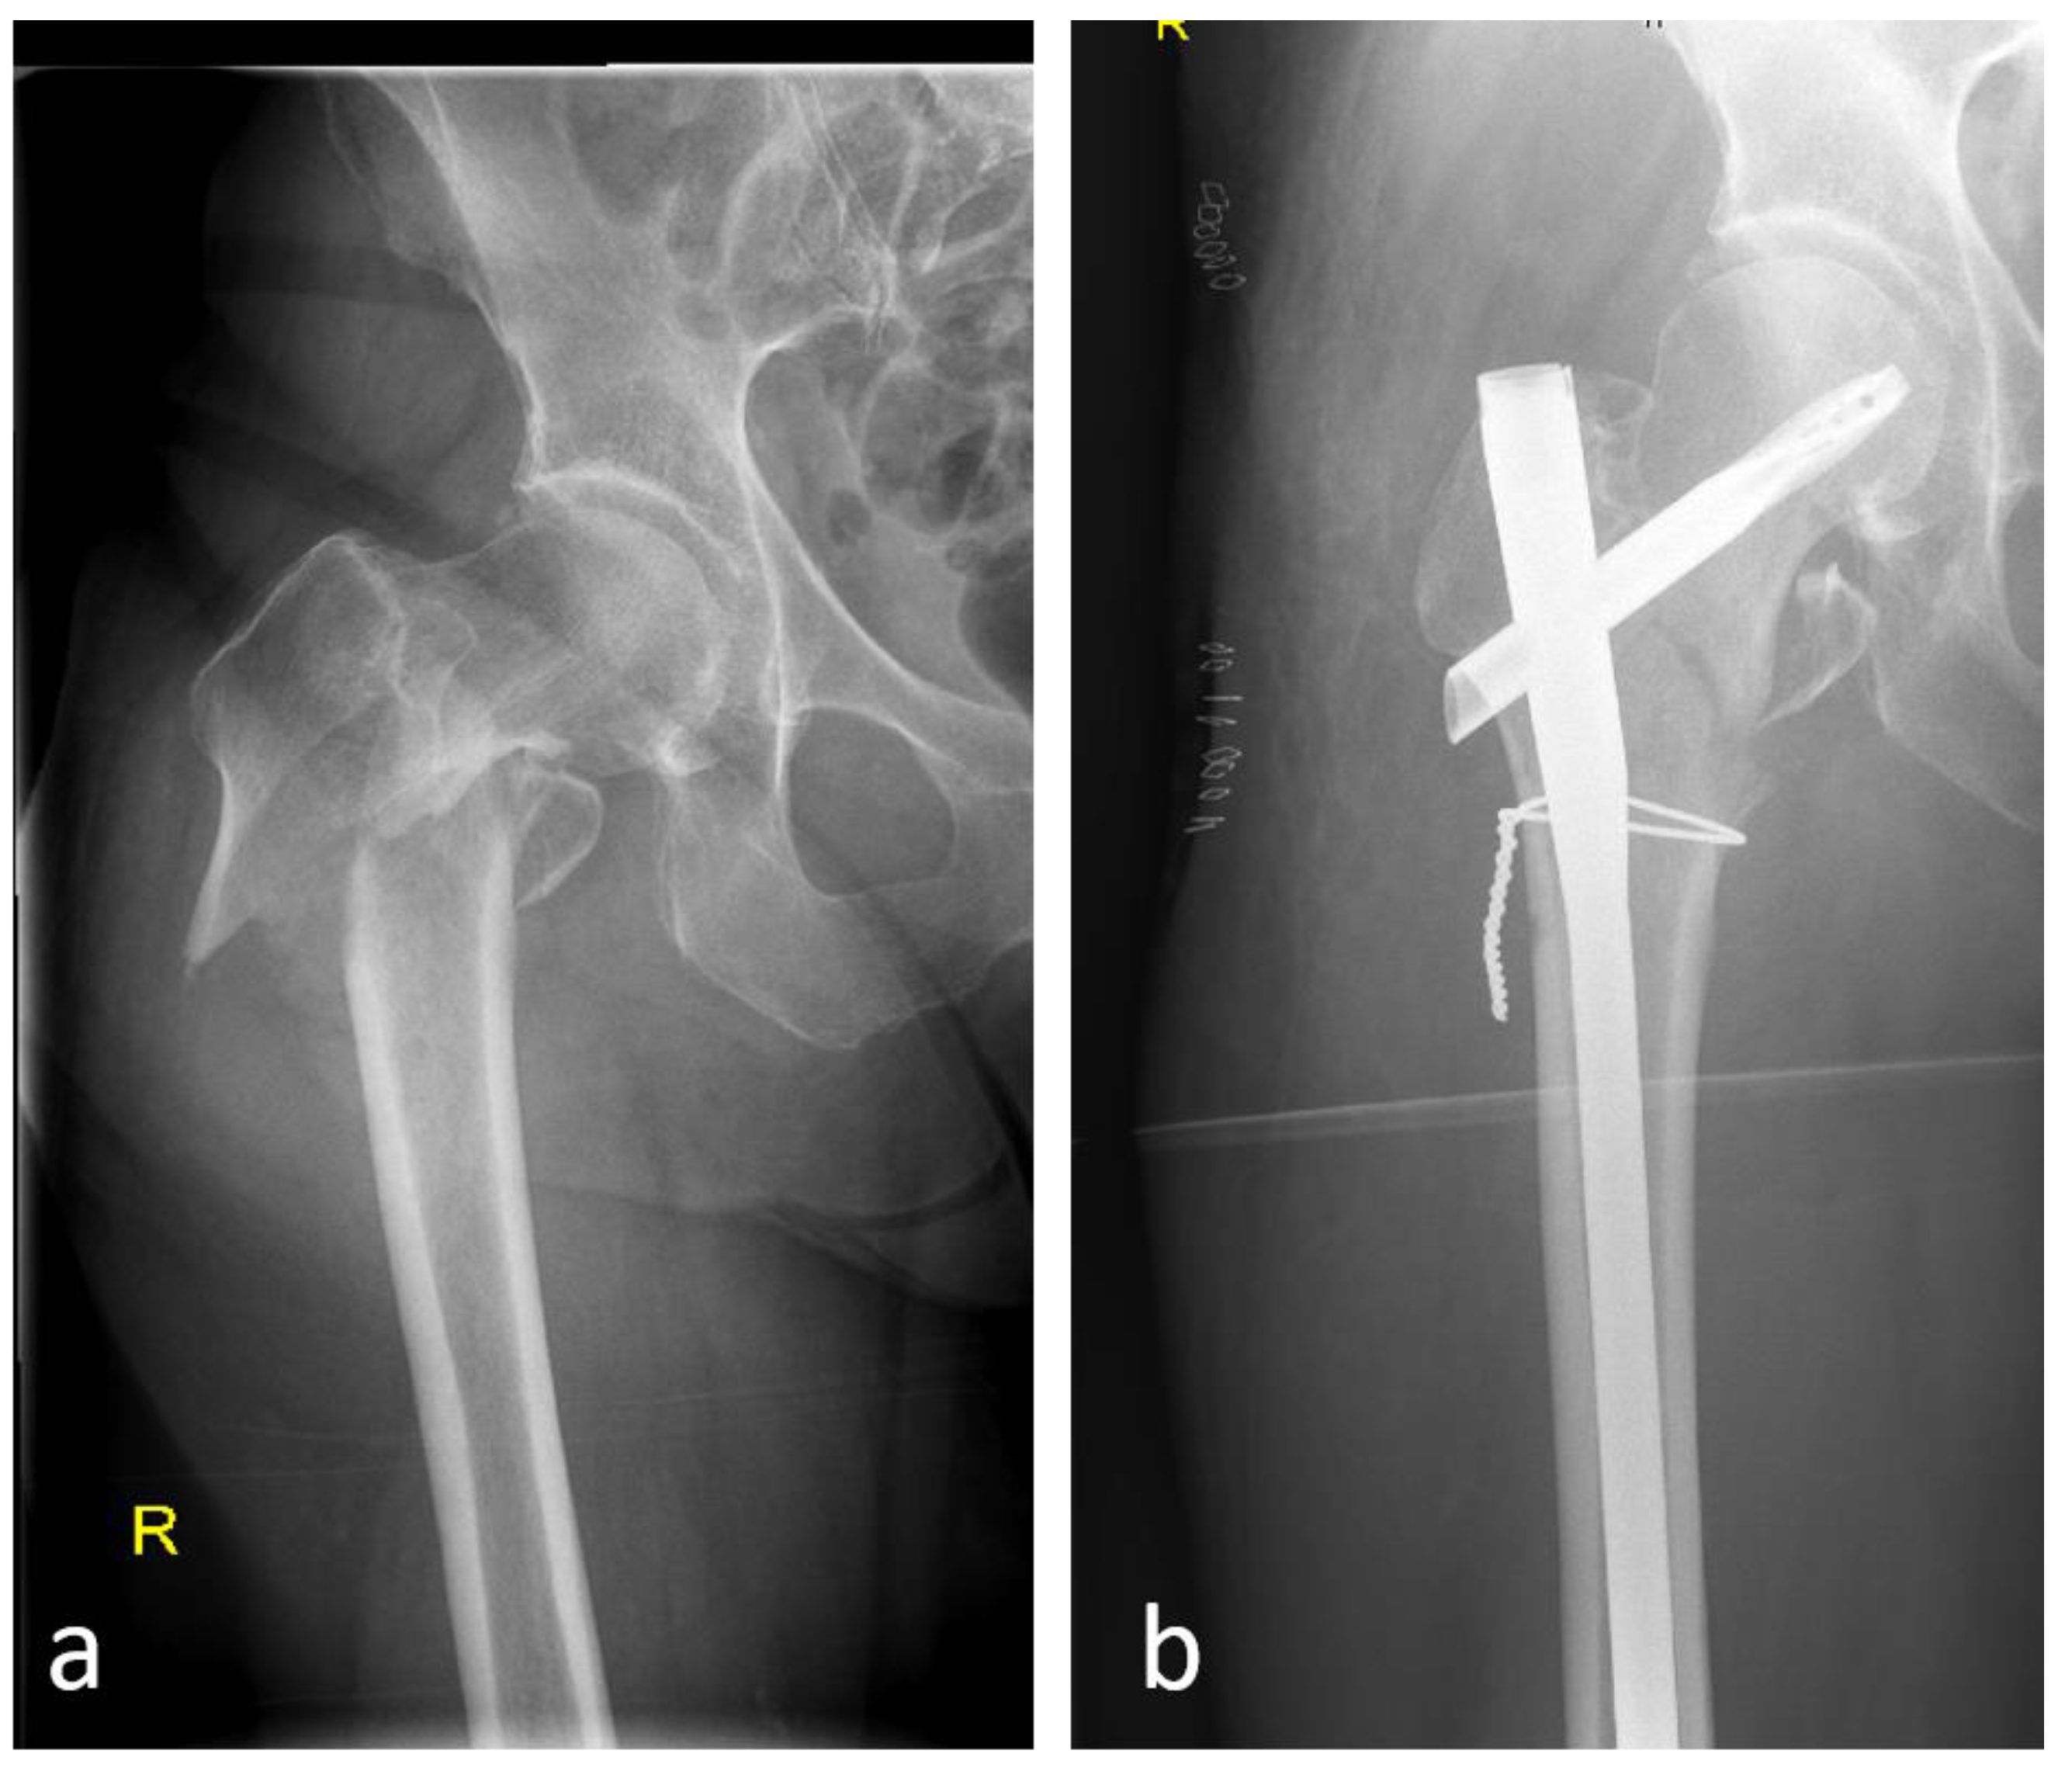

5.2. Open vs. Closed Procedure

5.3. Reconstruction With or Without Additional Cables and Plates

- Sharma, G.; GNK kumar Yadav, S.; Lakhotia, D.; Singh, R.; Gamanagatti, S.; Sharma, V. Pertrochanteric fractures (AO/OTA 31-A1 and A2) not amenable to closed reduction: Causes of irreducibility. Injury 2014, 45, 1950–1957. [Google Scholar] [CrossRef]